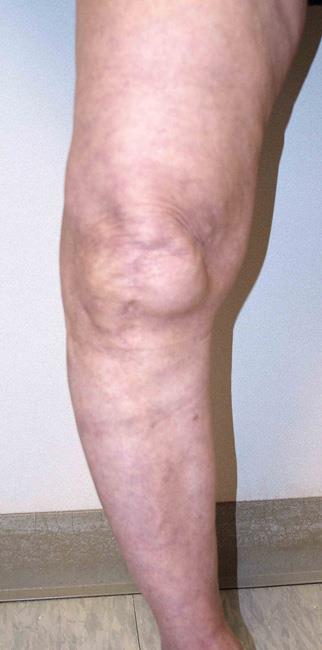

El reemplazo total de rodilla podría recomendarse a pacientes que tienen la rodilla arqueada, como se muestra en esta foto clínica.